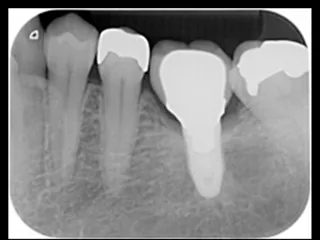

CASE No.4 大月 基弘 先生(大阪府大阪市開業)

Labrida 施 術 前

施 術 前 (レントゲン写真)

Labrida 施 術 後(2週後 )

PPD7㎜からPPD3㎜、

BOP(ー)に変化、炎症消失